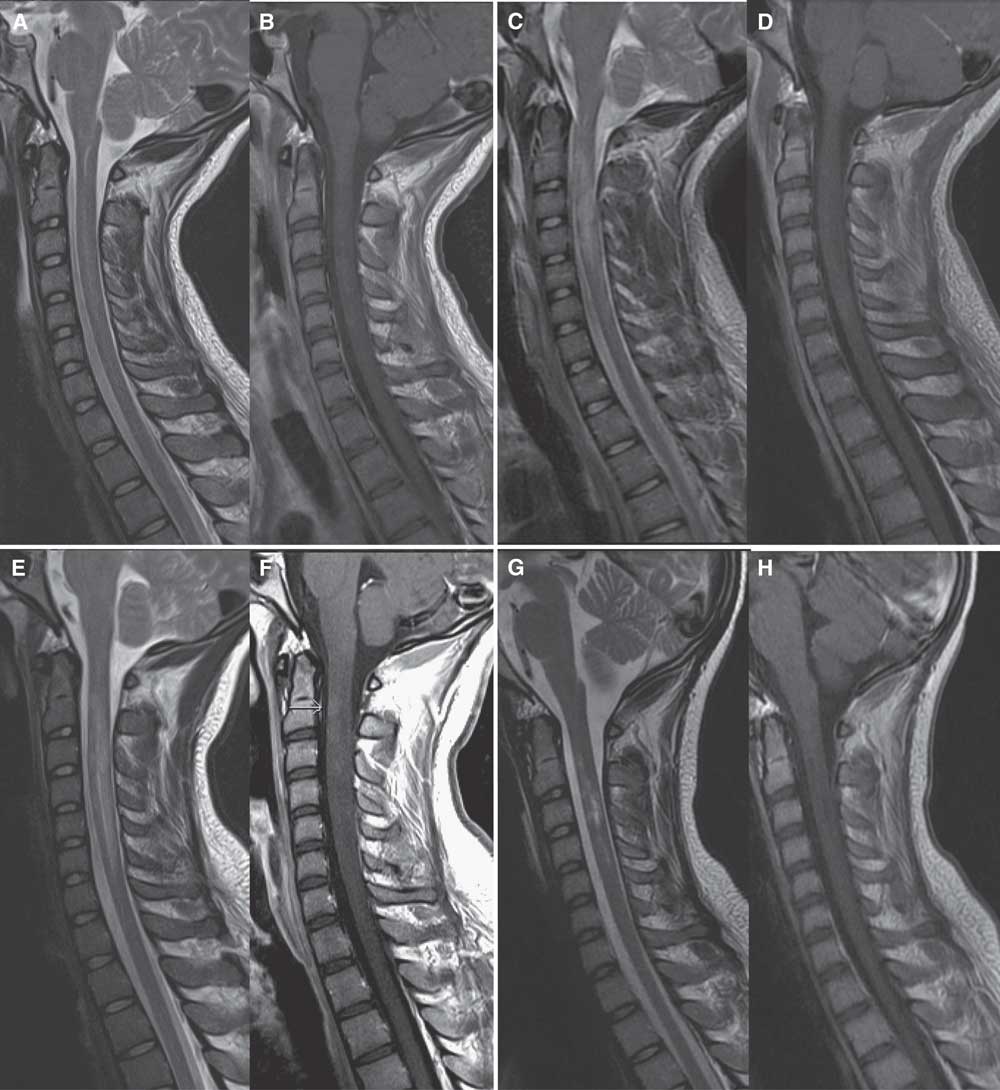

Figure 2 Sagittal MRI scan of the cervical spine in case 2. On admission, sagittal MRI of the cervical spine shows hyperintensity of the central spinal cord from C2-C5 levels on T2 images (A) with subtle corresponding enhancement on postgadolinium T1 images (B). After 4 days of high-dose IV methylprednisolone and three plasma exchanges, repeat MRI shows increased edema and hyperintensity on T2 images from C2-C5 (C) with cord expansion, and progressive cord enhancement on postgadolinium images (D). After completing a 5-day course of high-dose IV methylprednisolone and 14 plasma exchanges, repeat MRI shows further extension of cord involvement from C2-C6/7 levels with T2 hyperintensity (E) and increased enhancement on postgadolinium T1 images (F). Two weeks after completion of cyclophosphamide induction, repeat MRI shows resolving cord edema on T2 images (G) and resolution of cord enhancement on postgadolinium T1 images (H).

Repeat MRI (Figure 2C-D) on day 3 of PLEX showed worsening cord edema and increased enhancement. Sensory level on examination had ascended to C4. After 14 plasma exchanges, clinical status remained unchanged, and LETM had spread to C1-C6/7 on MRI (Figure 2E-F), with further increase in enhancement. Given his refractory clinical status and worsening MRI (despite PLEX and high-dose corticosteroids), cyclophosphamide induction (as described in case 1) was completed on day 16.Reference Weiner, Mackin and Orav 5 , Reference Partners 6 Within a week of induction, motor function began to improve rapidly. Repeat MRI (Figure 2G-H) 2 weeks later showed resolving cord edema and resolution of enhancement. One month later, he was discharged from the ICU and quickly transferred to inpatient neurorehabilitation where he continued a 4-month oral prednisone taper. No further immunosuppressive or immunomodulatory therapy was given. After 5 months of rehabilitation, he was discharged home. He had regained bladder and bowel control, and walked with a walker and ankle foot orthotic. Right deltoid was MRC 2, right bicep MRC 3, bilateral knee flexion MRC 3, left ankle flexion MRC 2, and the remainder of his power examination was MRC 4 or greater.